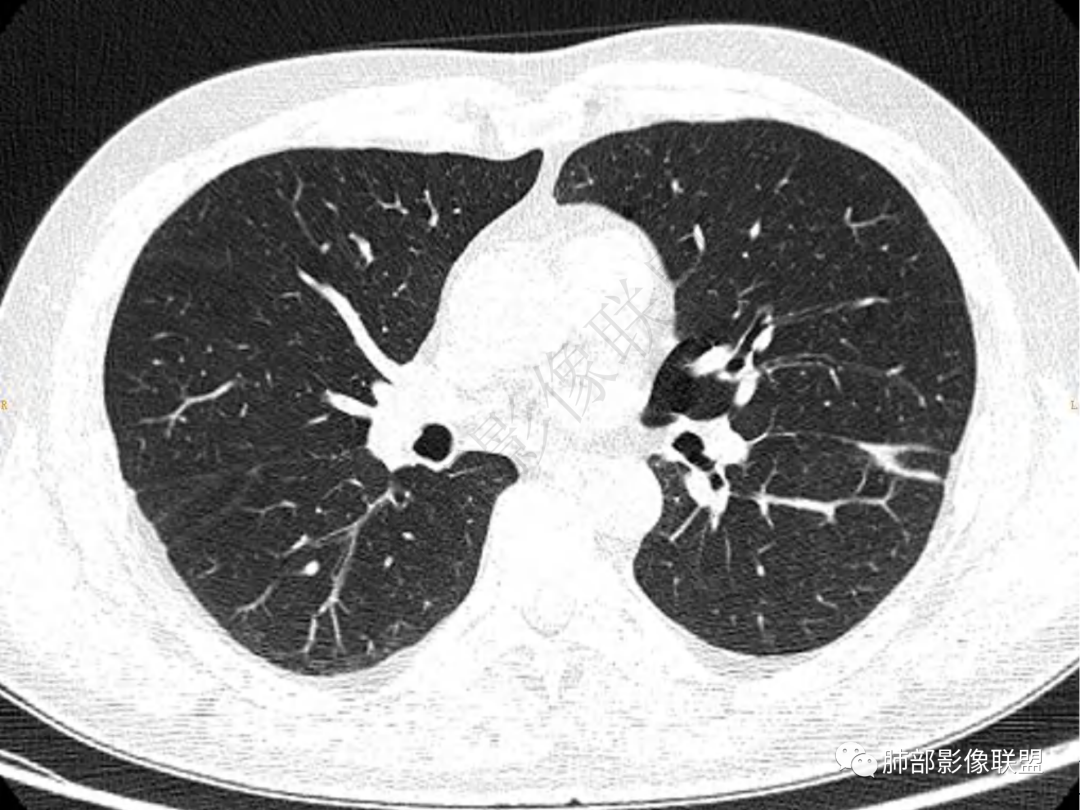

1.中年男性,咳嗽咳痰20余天,间断咯血2周

2.左肺下叶团片影,跨背段及内前基底段,实性部分类椭圆形,密度不甚均匀,可见毛刺及棘状突起,未见典型分叶及胸膜凹陷。病灶上下缘可见相应肺段支气管旁进侧出,管壁轻度增厚,未见狭窄阻塞。

3.周边较大范围磨玻璃影,边界相当模糊,小叶增厚明显。注意叶裂另一侧、左肺舌段亦可见磨玻璃影及增厚的小叶间隔。未见明确卫星病灶。

4.实性部分不均匀环形强化并显示一小范围低密度坏死区或空洞。较之肺窗,整体纵隔窗范围较小,提示病灶并不十分密实。抑或为不同时段图像。

5.双肺门及纵隔未见增大淋巴结。未见胸腔积液。

肺脓肿:可宽基底与胸膜相连,附近胸膜增厚——炎性特点

肺脓肿:边界模糊不清,或者块影为类圆形,无明显分叶,边缘平直为主,刀切征——炎性特点三、病灶周围特点:肺脓肿:病灶非远端有片状GGO——炎性特点四、近端支气管阻塞:肺脓肿:常有引流支气管伴管壁增厚或者支气管沿洞壁走行。五:坏死壁:肺脓肿:大多壁厚,少数壁薄,没有壁结节,内壁清楚光整——炎性特点

肺脓肿:环形强化,强化较显著。如出现明显囊壁样强化甚至边缘“憩室”样突出,高度支持肺脓肿。